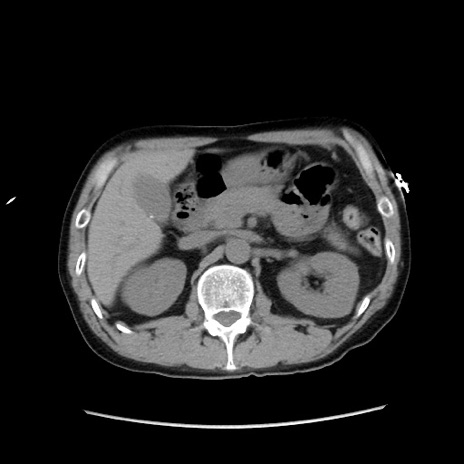

症例37(横断像)

【症例】40歳代 男性

【主訴】腹痛

【現病歴】4時間ほど前に電車に乗車中に臍部上より腹痛出現。徐々に増悪し起立困難となり、救急外来受診。生ものは数日食べていない。今朝お雑煮を食べた。

【身体所見】BT 36.8℃、BP 117/84mmHg、HR 91/min、SpO2 97%、苦悶様、腹部:臍上部広範囲圧痛あり、反跳痛±

【データ】WBC 8100、CRP 0.03